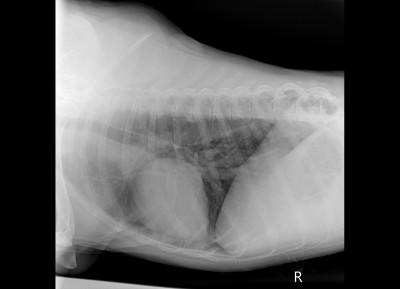

Рентген

Описание рентгена

Интересно, а изменения в бронхах на рентгене от диро или результат хронического бронхита?